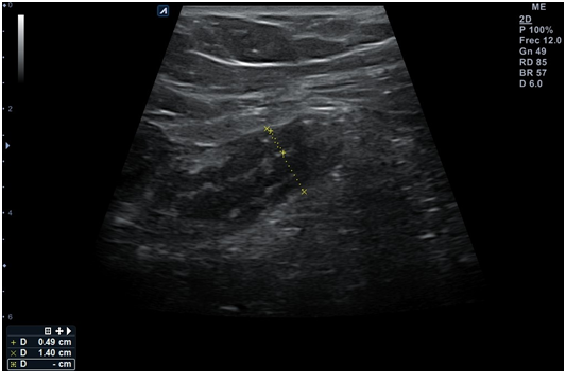

Al día siguiente el paciente acude a su Centro de Salud ya que persiste el dolor abdominal localizado en flanco derecho. A la exploración física destaca dolor la palpación fosa ilíaca derecha (FID) siendo más intenso a la descompresión. Se realiza ecoscopia dirigida con sonda lineal de alta frecuencia donde se visualiza en FID lo que parece un apéndice engrosado (14 milímetros), hipoecogénico, con paredes gruesas (hasta 5 milímetros) no compresible, grasa mesentérica periapendicular hiperrefrigente que se moviliza en bloque y pequeña cantidad de líquido libre periapendicular, con Blumberg ecográfico positivo. (Imagen 1)

Juicio clínico, diagnóstico diferencial, identificación de problemas

Ante la sospecha de apendicitis aguda se deriva al paciente a Urgencias hospitalarias para ser valorado por el Servicio de Cirugía, donde se vuelve a realizar ecografía de abdomen y se observa, apéndice veriforme en FID, calibre hasta 12 milímetros, con ligeros cambios inflamatorios en el mesoapéndice y flogísticos en Doppler color, asociado a Blumberg ecográfico. (Imagen 2)